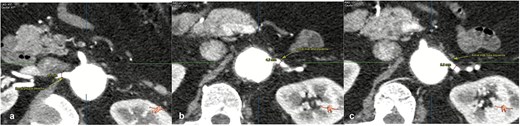

On admission, the patient was neurologically intact. Physical examination of the neck revealed a jugular venous pulse measuring 5 cm, with no carotid bruits. Both hemithoraces were well ventilated, and cardiac auscultation revealed regular rhythm with normal heart sounds and no gallops (S3 or S4). Abdominal examination demonstrated preserved peristalsis, a soft and non-distended abdomen, and a palpable, non-tender pulsatile mass in the mesogastrium. A systolic murmur graded IV/VI was auscultated over the mesogastric region. Peripheral vascular assessment revealed diminished distal pedal pulses with a capillary refill time of <2 s. A comprehensive imaging workup confirmed the presence of a complex aortoabdominal aneurysm involving both the suprarenal and infrarenal segments (Figs 1–3). Aneurysm dimensions are detailed in Table 1.

Contrast-enhanced thoraco-abdominal computed tomography (CT) with IVD at superior mesenteric artery level (a), celiac trunk level (b), renal arteries level (c).